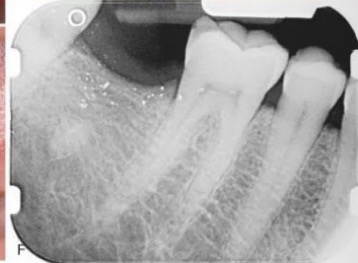

CHẨN ĐOÁN?

NHIỄM SẮC SÀN MIỆNG liên quan R36 có miếng trám Amalgam